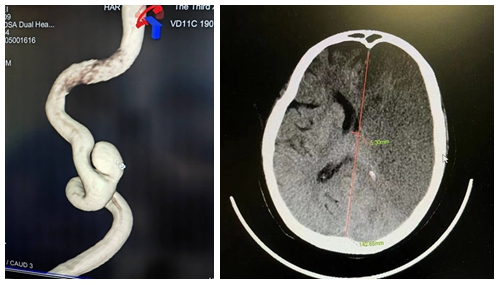

患者沈先生在外院行下颌骨肿瘤复发切除手术后颈部大血管出血,后并发大面积脑梗昏迷转至本院。入院CTA显示双侧顶枕叶大面积缺血梗塞灶,脑肿胀,左侧颈内动脉C1段动脉瘤。

湘雅三医院神经外科脑血管组姜交德、卢韶华医生团队紧急行动,综合分析病情后认为目前患者的治疗存在三大难点:1.患者动脉瘤合并脑梗,围手术期的血压控制很关键,血压高了,就可能动脉瘤破裂,血压低了,又怕脑梗塞加重;2.这个病人既要做开颅,术后要止血,又要做介入,介入需要使用抗血小板的药物,围手术期出血的风险也会比一般的手术要更大;3.这个动脉瘤的载瘤动脉S形扭曲,血流导向装置着陆及充分贴壁有很大难度。

任何一点处理不当,都可能导致患者死亡。最终团队经过综合研判决定首先以最快速度为患者行去骨瓣减压术保住性命。术后入神经外科重症监护病房,通过医护精心治疗于3月28日转入普通病房。接下来团队面对患者复杂病情冲破一道道难关,于5月6日在全麻插管下为患者行“左侧颈内动脉载瘤血管内血流导向支架置入术+弹簧圈动脉瘤栓塞术”。面对复杂扭曲的血管,仅仅耗时2小时就成功完成了手术。